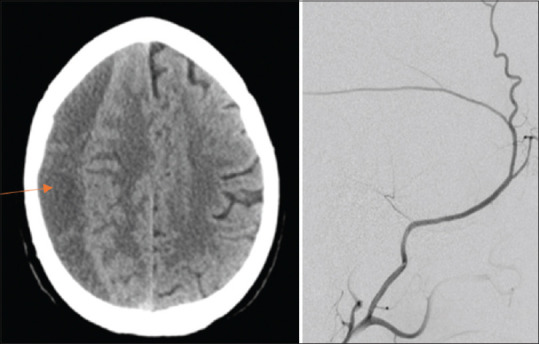

Chronic subdural hematoma (c-SDH) is a frequent and serious neurological disease. It develops due to hemorrhage to the subdural space, mainly caused by head trauma. The middle meningeal artery (MMA) plays a critical role in the supply of blood to c-SDH. The decision on the type of treatment for c-SDH depends mainly on clinical and imaging evaluation. In cases in which patients are critically ill, the hematoma must be evacuated immediately. For this purpose, surgery is generally accepted as the mainstay of treatment. Among surgical techniques, twist-drill craniotomy, burr-hole craniotomy, and craniotomy are the three most used. The recurrence rate of c-SDH after surgery is an important problem with a rate of up to 30%. The technical success classification embolization of MMA (EMMA) has emerged as an effective and safe option for the treatment of c-SDH, especially those that recur. EMMA is commonly used as an adjunct to surgery or less frequently alone. The technical success of EMMA has been a promising minimal invasive strategy as an alternative or adjunctive therapy to surgical methods. Polyvinyl alcohol is the most widely used among various embolizing agents, including n-butyl cyanoacrylate, coil, and gelatin sponge. EMMA has been shown to prevent the formation or recurrence of c-SDH by eliminating blood flow to the subdural space. Complication rates are low. The large-scale comparative prospective will ensure efficacy and safety. This article aims to highlight the current information about EMMA in patients with c-SDH.